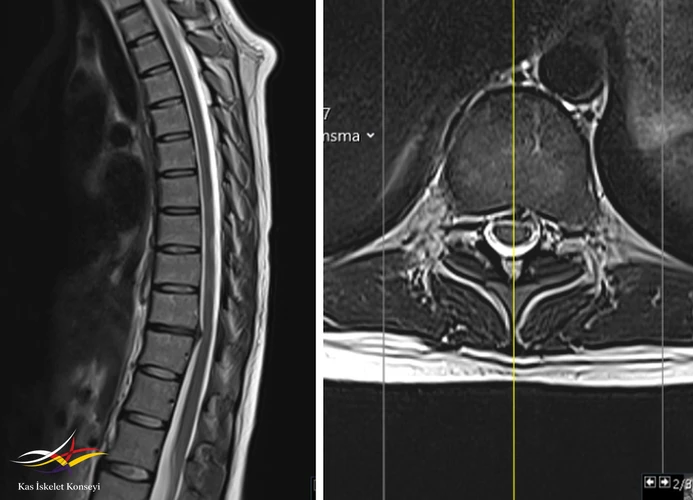

İncelemeler: HLA B27 negatif. Torasik MRG: Alt dorsal seviyede disk hernisi mevcut. Belirgin bir nöral bası yok.

Sırt ağrısını açıklayacak başka bir neden bulunamaması nedeniyle, tek seviyede saptanan bu alt torasik dejenere disk seviyesinin semptomların kaynağı olduğu düşünüldü. BT'de bu seviyede saptanan ligamentum flavum kalınlaşmasının bu seviyedeki mekanik yüklenme ve anormal biyomekaniğin bulgusu olduğu düşünüldü. Tanı tedavi amaçlı faset + epidural enjeksiyon planlanabileceği; egzersizin ve korse kullanımının uygun olduğu; ağrının tüm bu konservatif tedavilere yanıt vermemesi ve günlük hayatı etkileyecek seviyede olması durumunda son seçenek olarak basit diskektomiden ziyade bir stabilizasyon operasyonuna gidilebileceği tartışıldı.